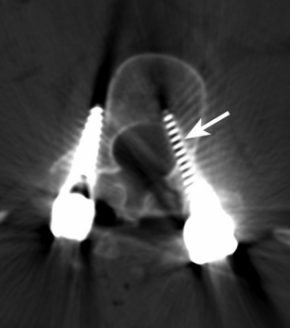

图3 CT显示螺钉移位

植入物相关并发症包括植入物松动、移位、拔出或断裂等,可能导致血管、神经和脏器损伤。Weiss等综述性研究认为螺钉移位是微创经椎间孔腰椎融合术常见并发症之一。Liu等通过对3936例腰椎手术患者的临床资料进行分析,发现21例因螺钉移位再次手术。Ghobrial等的系统综述显示,在2052例患者中有37例在腰椎后路减压融合术后发生神经功能损伤,其中11例是螺钉移位造成。Khalifa等研究纳入51例接受腰椎融合术的患者,平均随访24个月,发现1例因螺钉移位而再次手术。Šámal等发现,51例腰椎间盘退变患者行微创腰椎后路椎间融合术后,发生5例螺钉移位,1例再次手术调整植入物。Tsai等统计分析了10350例多种脊柱手术患者临床资料,发现4 984例螺钉植入患者中有41例术后1周内发生螺钉移位,其中11例手术调整螺钉,余30例拔除螺钉后未重新植入。除螺钉移位需要再次手术治疗外,骨水泥外渗的患者必要时也需要采取手术治疗。Janssen等报道165例接受胸腰椎骨水泥增强椎弓根螺钉手术的脊柱肿瘤或脊柱退行性疾病患者中,有10例发生骨水泥硬膜外渗漏,其中2例需要再次手术。螺钉和骨水泥等植入物是否稳定与骨质有很大的关系。Lee等提出骨质疏松症患者脊柱融合手术后更容易发生植入物并发症。Khalid等也提到,接受腰椎融合术的骨质疏松症或骨质减少患者术后并发症发生率较高,包括椎弓根螺钉松动等,部分患者需要再次接受手术治疗。植入物并发症一般发生在脊柱手术后较长时间,可能由于患者活动不当造成。因此,手术后应详细告知患者避免不当的活动方式,对于骨质疏松的患者更应提高警惕,术后帮助患者改善骨质,减少再次手术风险。